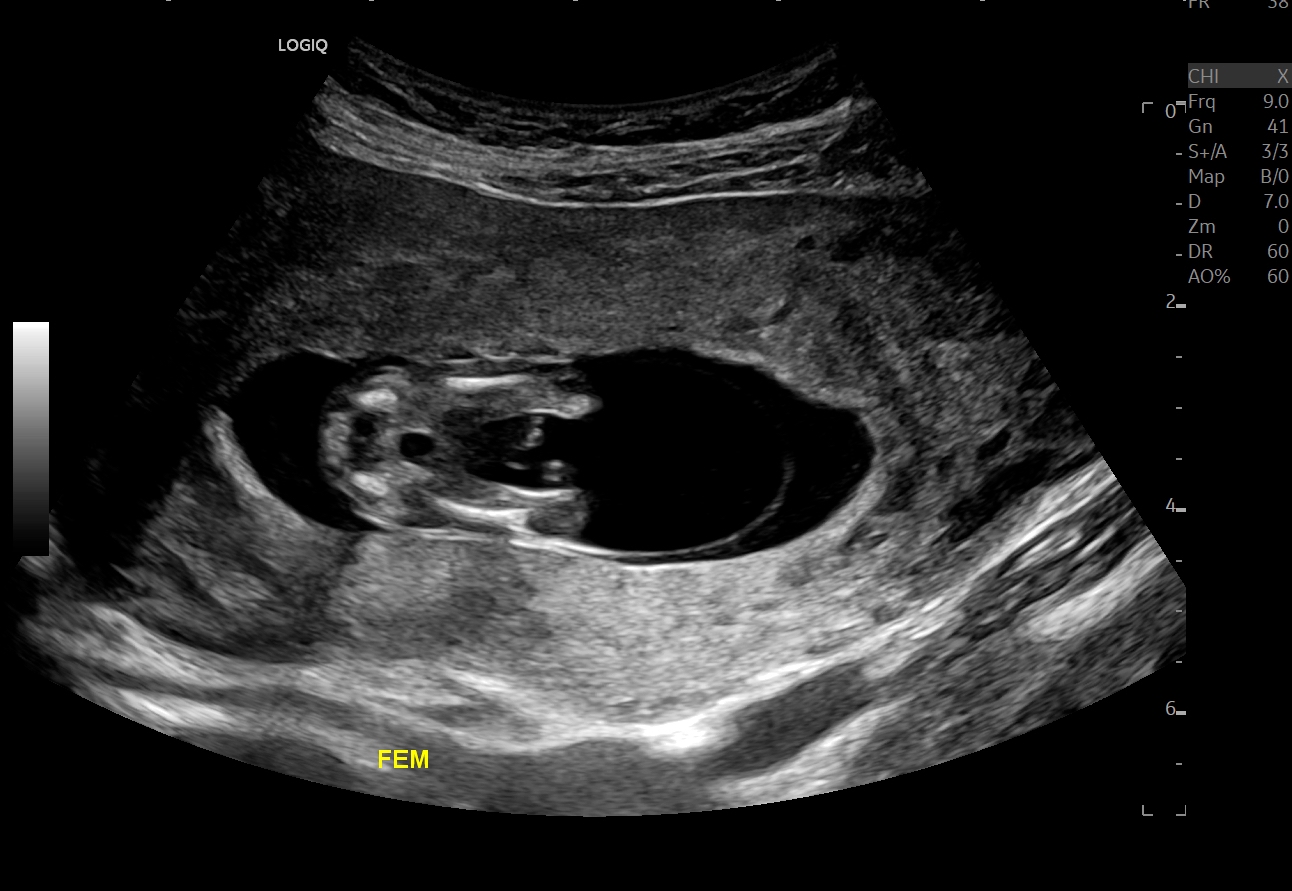

Just got home from our 13 week scan. Would love your thoughts on whether baby is pink or blue! The nub looks girly to me but then later on in the scan the sonographer went down around in a type of potty shot and I thought I saw something between the legs, so now I'm not so sure (didn't get a photo when she went in for the potty shot, she said it was too early to tell)... are potty shots reliable for gender at 13 weeks? If I hadn't seen that potty shot I'd have guessed girly?

Edit: Just talked to DH about the potty shot and he said that was a shot of the baby's head, lol! I’ve included an earlier shot she did of baby’s femurs (legs) in case that gives any clues.

Attachment 43634